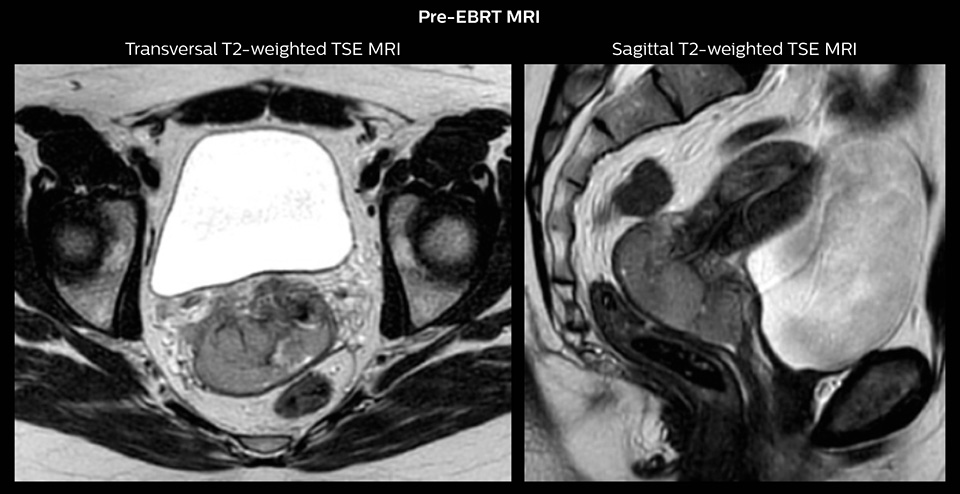

“In patients referred for cervical cancer treatment at our hospital, MRI has already been part of the diagnostic process. Before initiation of EBRT, PET-CT and MR treatment planning scans are acquired with the patient in treatment position on flat table top.

The images are fused and used for MRI-guided target definition of the primary tumor and for PET-guided definition of pathological lymph nodes.

Then we perform pre-brachytherapy MRI within one week before the first brachytherapy session. This MRI exam is done with a dummy applicator in place to establish the geometry we are going to see at brachytherapy. This MRI exam allows us to see how the tumor responded to EBRT and we also use it to decide which kind of applicator the patient needs. For instance, if we see a very advanced tumor with poor regression, we need a more advanced applicator which combines intracavitary and interstitial brachytherapy.”

Stage IIB cervix cancer patient with a primary tumor with width of 6.0 cm and proximal/distal infiltration of left/right parametria at diagnosis. The patient had one PET-positive external iliac lymph node.

The patient was treated with external beam radiotherapy (EBRT) and concomitant chemotherapy. EBRT was delivered as IMRT with daily IGRT and a total dose of 45 Gy in 25 fractions to the pelvis and 55/25 fractions to the PET-positive lymph node. There was good tumor response during therapy and towards the end of EBRT the primary tumor had regressed to 3.8 cm width and proximal parametrial infiltration.

One week prior to the first brachytherapy fraction, pre-planning was performed. Pre-planning involved insertion of intracavitary tandem-ring applicator and MR imaging with applicator in place.

“The target definition is based on T2-weighted images. We recommend planning the sequence orientation relative to the applicator, so we perform a para-transverse imaging series, and also para-sagittal and para-coronal sequences,” says Dr. Tanderup.